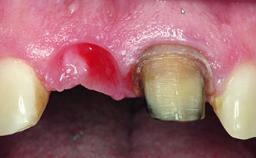

A healthy 37-year-old female patient was referred for a consultation on the replacement of missing tooth 21 with an implant-supported restoration. She stated that several years previously the tooth had been traumatically avulsed following a motor vehicle accident. The tooth was replaced with a three-unit fixed partial denture (FPD) immediately afterwards. Over time, she became disillusioned with the FPD and looked for a different option, including orthodontic therapy. She presented still in her orthodontic appliances, with the pontic sectioned free from the FPD but attached to the archwire. Her orthodontist felt that orthodontic treatment had been successfully completed, but nevertheless referred her before removing the appliances in case adjustments were necessary.

Soft Tissue Anatomy Intact Defective

Soft Tissue Contour and Volume Slightly compromised